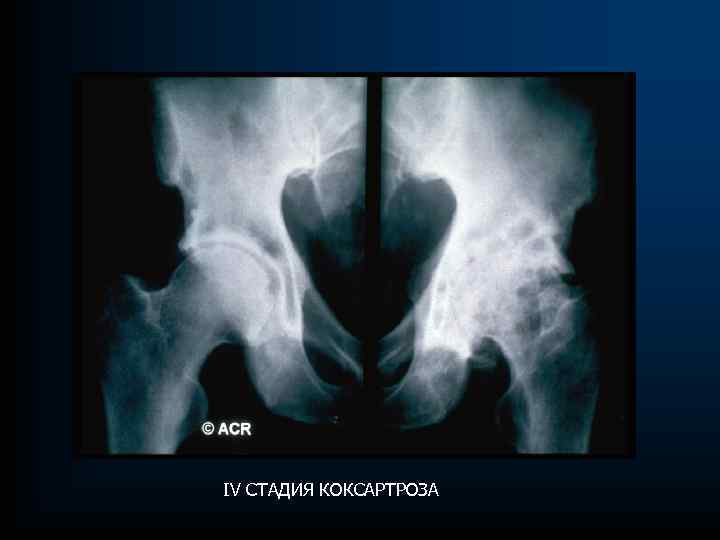

РЕНТГЕНОЛОГИЧЕСКАЯ СТАДИЯ ПО (Kellgren and Lawrence) стадия 0 – отсутствие ренгенологических признаков; стадия I –мелкий остеофит– сомнительный ОА; стадия II – четкий остеофит, неизмененная суставная щель – минимальный ОА; стадия III – незначительное сужение суставной щели – умеренный ОА; стадия IV – значительное сужение суставной щели со склерозом субхондральной кости

РЕНТГЕНОЛОГИЧЕСКАЯ СТАДИЯ ПО (Kellgren and Lawrence) стадия 0 – отсутствие ренгенологических признаков; стадия I –мелкий остеофит– сомнительный ОА; стадия II – четкий остеофит, неизмененная суставная щель – минимальный ОА; стадия III – незначительное сужение суставной щели – умеренный ОА; стадия IV – значительное сужение суставной щели со склерозом субхондральной кости

IV СТАДИЯ ОА

IV СТАДИЯ ОА

IV СТАДИЯ КОКСАРТРОЗА

IV СТАДИЯ КОКСАРТРОЗА